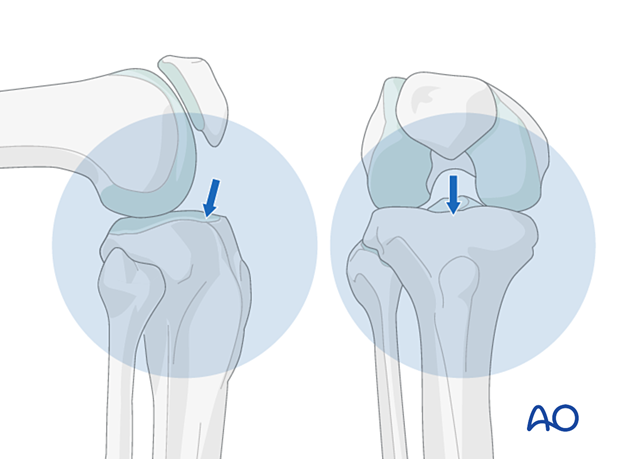

It is imperative to obtain appropriate AP and lateral views of the proximal tibia to ensure that the proper entry site for the tibial nail is obtained. A proper AP view has the lateral border of the tibial plateau bisect the fibular head. A proper lateral view has the femoral condyles superimposed on each other. The entry point for a tibial nail on the lateral view should be at the anterior edge of the joint line and on the medial aspect of the lateral tibial spine on the AP view.

Using fluoroscopy, with the appropriate AP and lateral views, a preliminary guide wire helps locate the proper entry site. Various cannulated instruments can be inserted over such a pin. Alternatively, a solid awl can be used for the same purpose. Make sure that the location is correct before the full opening is created.

Insert the guide wire parallel but posterior to the tibial crest, and thus in the center of the medullary canal.

Press the guide wire into the bone so the tip does not slip. While entering the bone, correct the guide wire alignment by pushing the proximal end of the wire posteriorly. This brings the wire almost in line with the axis of the tibia, as illustrated.

The illustration shows proper guide wire placement in the frontal plane. It is essential that the surgeon takes frequent AP and lateral fluoroscopic views while the guide wire is inserted to ensure that the proper trajectory of the guide wire is obtained.